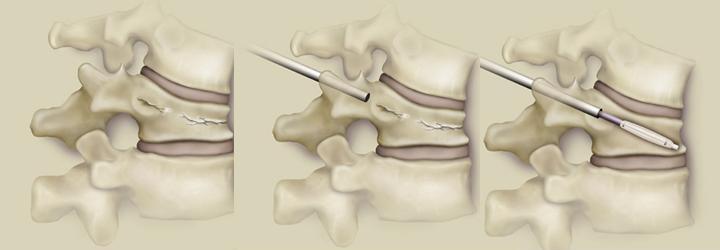

ΠΕΡΙΓΡΑΦΗ ΤΕΧΝΙΚΗΣ: Η επέμβαση συνιστάται στην έγχυση ειδικού τσιμέντου, μέσα από μικρές κάνουλες που μπαίνουν διαδερμικά. Για το σκοπό αυτό απαιτούνται μία ή δύο τομές της τάξεως του μισού εκατοστού. Η τεχνική παριστάνεται σχηματικά παρακάτω: αρχικά βλέπουμε τον "καθισμένο" σπόνδυλο που έχει υποστεί κάταγμα. Στη μέση φαίνεται η εισαγωγή της κάνουλας και στη δεξιά η εισαγωγή του μπαλονιού:

To μπαλονάκι φουσκώνει προοδευτικά ανατάσσοντας το κάταγμα,όπως φαίνεται στη μεσαία εικόνα και αποσύρονται αφήνοντας την νεοδημιουργειθήσα κοιλότητα:

Μέσα από την κάνουλα εγχύεται τσιμέντο μέχρι να πληρωθεί η κοιλότητα και τελικά αποσύρουμε την κάνουλα.